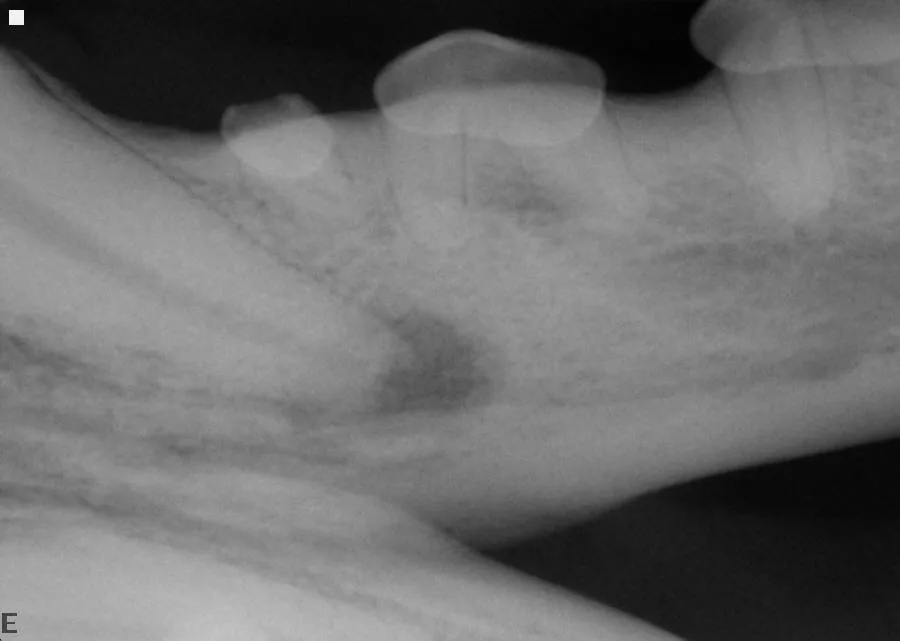

A parulis is an opening of an intraoral sinus tract in the oral mucosa; hidden periodontal disease is often indicated if the parulis is within the gingiva (Figures 3 and 4). Periodontal disease is caused by a subgingival biofilm (an adherent bacterial community living in an exopolysaccharide matrix that protects the bacteria and allows cooperation of the microorganisms) that results in loss of attachment of the periodontium (ie, gingiva, alveolar bone, periodontal ligament, cementum), regardless of the amount of plaque or calculus on the supragingival crown. Periodontal disease is predominately a subgingival disease, so general anesthesia and intraoral radiographs are required. Extraction is often necessary for periodontal disease associated with a parulis. If the parulis is within the oral mucosa, it is likely caused by endodontic disease, and root canal treatment may be an option. A parulis at the mucogingival junction might be caused by either periodontal or endodontic disease.

Combined vertical and horizontal bone loss of the distal and buccal roots of tooth 108 from the patient in Figure 3, resulting in almost complete bone loss. The tooth has a wide pulp canal compared with other teeth, indicating the pulp in this tooth died a long time ago (combined periodontal–endodontic disease). Surgical extraction is the only option in this case. The pulp chambers in tooth 106 wider than the other teeth, indicating that the pulp in this tooth is also necrotic and requires extraction.